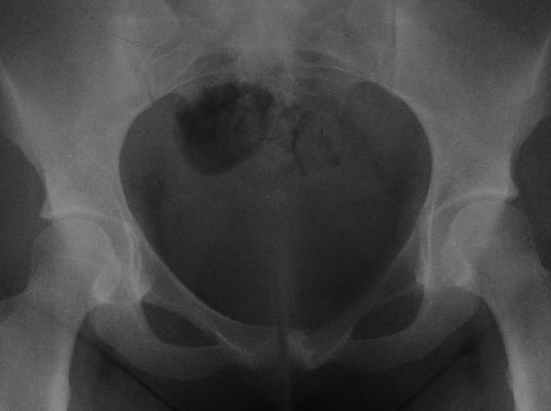

пациентка 20 лет, в сентябре 2005 года почувствовала боли в паху. На снимках заподозрили остеомиелит, лечили антибиотиками без эффекта. К онкологу попала в январе2006. Биопсия в марте 2006 - остеобластокластома. Местные онкологи от операции отказываются.

Вопрос с планом лечения (надо ли замещать деффект и чем) и где оперироваться (опыт подобных операций).В приложении рентгенограммы в динамике (2005 сентябрь, декабрь, 2006 апрель).

Показал случай нашим онкологам. Они советуют сделать КТ, чтобы выяснить распространение процесса в симфизе и вертлужной впадине. Если распространения нет, то у нас обычно просто выполняют резекцию лонной кости без замещения дефекта.